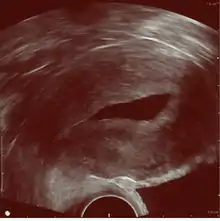

Left hydrosalpinx on gynecologic ultrasonography

Gynecologic ultrasonography or gynecologic sonography refers to the application of medical ultrasonography to the female pelvic organs (specifically the uterus, the ovaries, and the fallopian tubes) as well as the bladder, the adnexa, and the recto-uterine pouch. The procedure may lead to other medically relevant findings in the pelvis.This technique is useful to detect myomas or mullerian malformations.

The examination can be performed by transabdominal ultrasonography, generally with a full bladder which acts as an acoustic window to achieve better visualization of pelvis organs, or by transvaginal ultrasonography with a specifically designed vaginal transducer. Transvaginal imaging utilizes a higher frequency imaging, which gives better resolution of the ovaries, uterus and endometrium (the fallopian tubes are generally not seen unless distended), but is limited to depth of image penetration, whereas larger lesions reaching into the abdomen are better seen transabdominally. Having a full bladder for the transabdominal portion of the exam is helpful because sound travels through fluid with less attenuation to better visualize the uterus and ovaries which lies posteriorly to the bladder. The procedure is by definition invasive when performed transvaginally. Scans are performed by health care professionals called sonographers, or gynecologists trained in ultrasound.